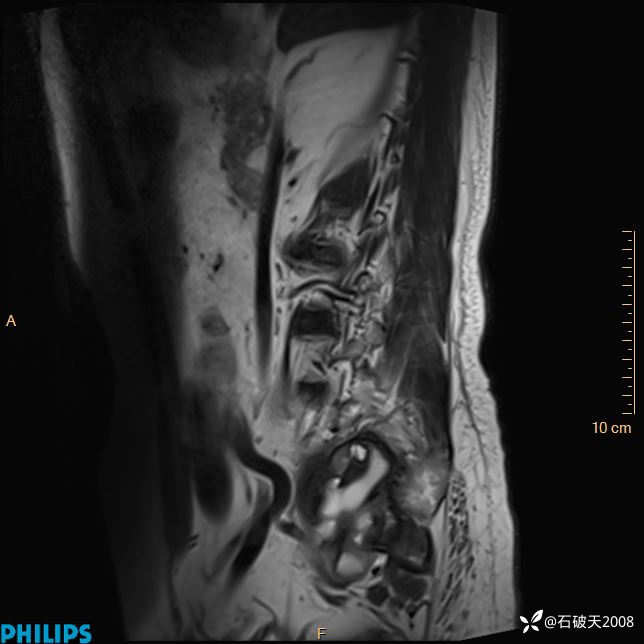

2023年3月份MRI影像

T2矢状位压脂